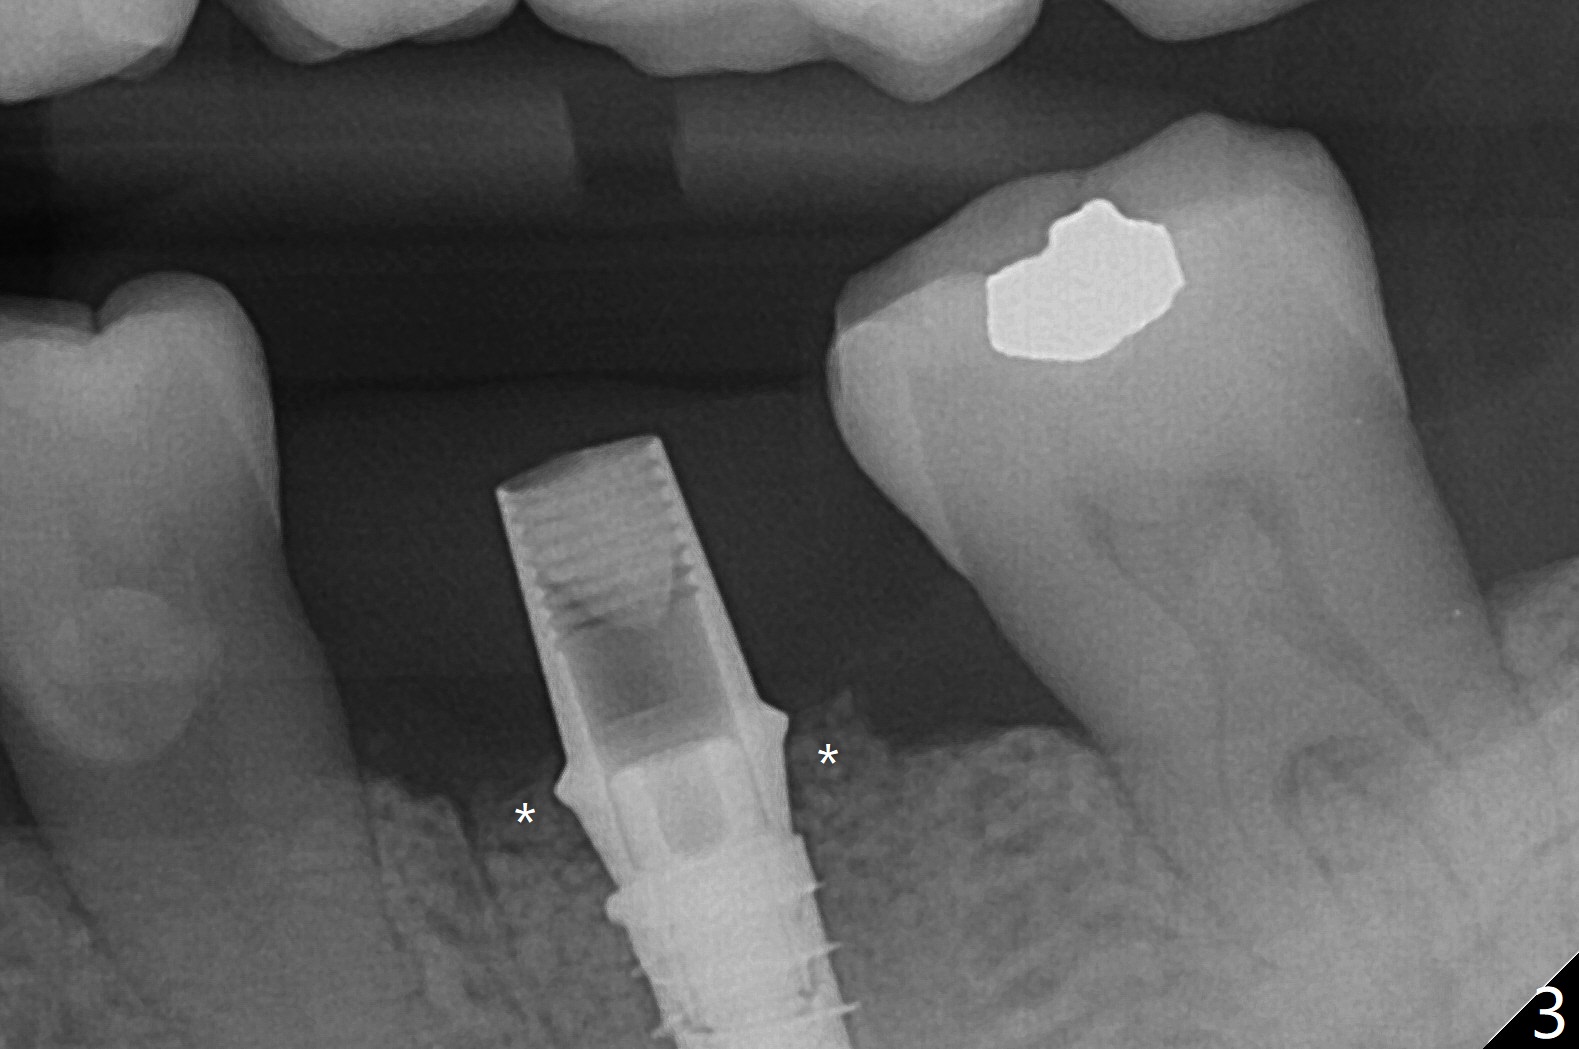

左下第一磨牙拔除后,放置导板,最细钻头到深度,没有偏移: 在中隔正中(图一),细短植体植入后基本保持在中隔之中(图二),扭力~30Ncm,在近中,远中剩余牙槽窝植骨后(图二:*),安置修复基台。制作临时牙冠后,在基台周围再次放置骨粉(图三)。术后7天牙周敷料脱落,12天复查时,临时牙冠周围软组织(角化龈,龈乳头)正常(图四)。